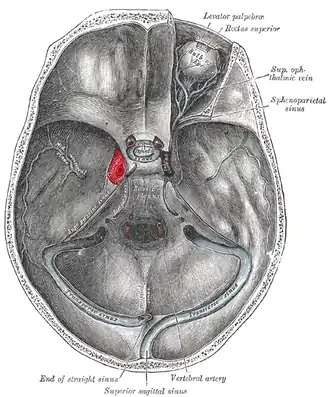

Cavernous sinus (center, labeled "SIN. CAVERN.") | |

The sinuses at the base of the skull. Cavernous sinus labeled in red | |